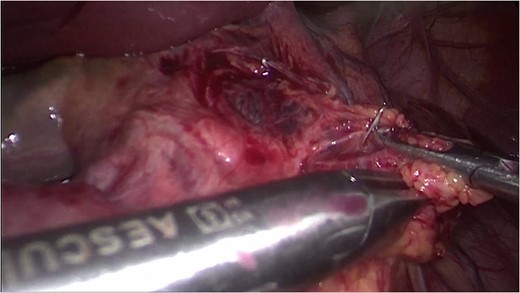

Hepatoduodenal ligament, with visualization of the herniated colon (a) and mesocolon in torsion.